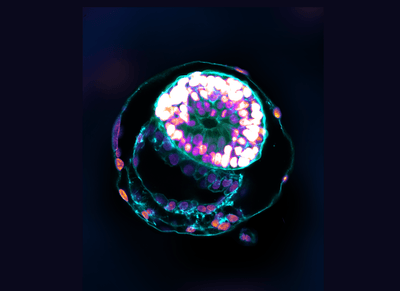

Scientists have created "complete" human embryos using stem cells in a lab and managed to grow them outside the womb for 14 days. Fear not, this is not an attempt to make a living Franken-baby in a test tube or anything of the kind. Instead, the researchers aim to provide a model that can help increase our understanding of a crucial moment in embryo development that impacts the risk of miscarriage and birth defects.

The rest of this article is behind a paywall. Please sign in or subscribe to access the full content.Two teams of scientists – one from Yale School of Medicine and another from the University of Cambridge – have recently announced success stories in creating synthetic embryo-like models, but this latest research from the Weizmann Institute of Science in Israel goes a step further as their embryo models have a significantly more complex, self-organized structure.

The work aims to shed light on a stage of embryo development called gastrulation that occurs two to three weeks after conception. It’s a critical stage of development, but scientists know very little about this fundamental turning point in early development as the microscopic embryo is buried in the womb at this time.

Just like previous studies, the embryo models were not created using sperm, fertilized eggs, or a uterus. The researchers managed to coax human stem cells into organizing themselves into synthetic embryo-like models that closely resemble a human embryo.

Based on their previous work with mouse embryos, the team took pluripotent stem cells – "blank slate" cells that have the potential to differentiate into many different cell types – and made them revert these cells to an earlier "naive" state.

Through a series of intricate steps, this enabled them to produce self-assembling models that closely mimicked the 3D architecture and key developmental landmarks of human embryos from 7 days after fertilization, around the time it implants itself in the womb, to 14 days after fertilization.

The researchers claim their work goes further than the previous attempts as the model human embryos contain key cell types that are essential to the embryo’s development, such as those that form the placenta and the chorionic sac, which the other studies did not.